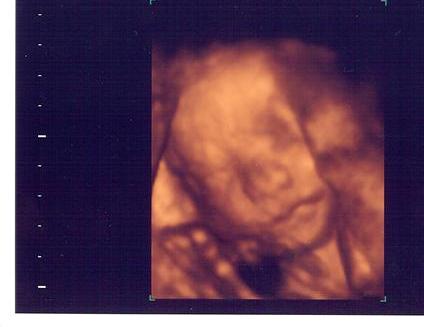

Just got back from 3D sonogram at Impact!!

Here she is!!

Image Attachment(s):

You got some great pics!!!! My little girl is very shy! She shouldn't move, so we only got profile shots!!!! Then, she put her hand in front of her face! LOL It was still so amazing to see her moving around and in 3D form. Congrats!